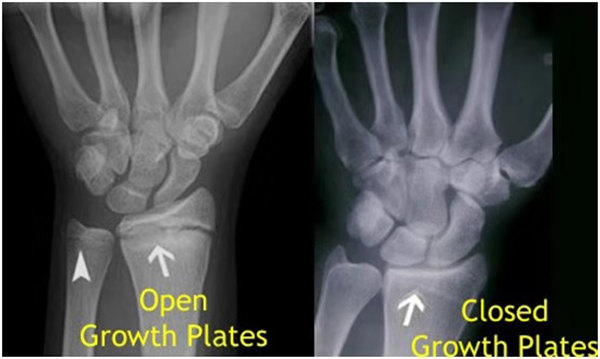

我們都知道,人體的高矮是由骨骼的生長(zhǎng)發(fā)育決定的,特別是下肢長(zhǎng)骨。長(zhǎng)骨呈長(zhǎng)管狀,在長(zhǎng)骨的兩端有一種專管骨骼生長(zhǎng)的骺軟骨,它與干骺端之間有一盤狀軟骨結(jié)構(gòu)稱為骺板(線),在幼兒的X光片上表現(xiàn)為一條較寬的透光帶。 (見下圖)

未成年時(shí)隨著年齡的增加骺軟骨端不斷骨化,骨骼就不斷增長(zhǎng)。當(dāng)骨骺線完全閉合時(shí)骨骼就停止生長(zhǎng),個(gè)子也就不再增長(zhǎng)了。一般骨骺端完全閉合的年齡是18~20歲左右。

骨骺線提前閉合最多見的情況是性早熟,而這也是很多醫(yī)生專家建議孩子進(jìn)行骨齡測(cè)量的原因之一。另外,在兒童時(shí)期大量補(bǔ)鈣也會(huì)使骨骺端提前過早閉合。